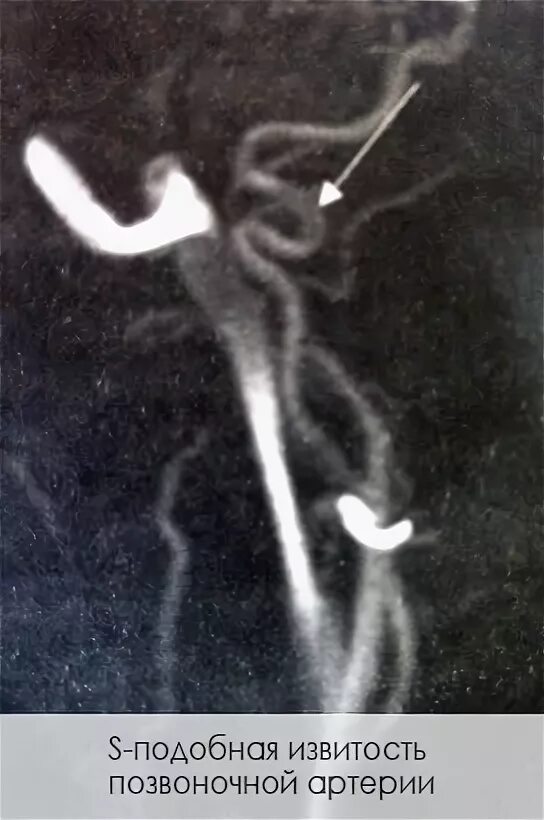

С образная извитость артерий